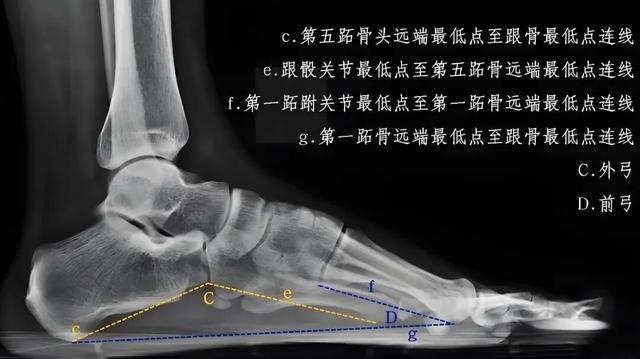

临床上诊断平足的“金标准”是拍摄负重位X片,如上图所示,通过测量特定位置角度,就能客观判断足弓塌陷程度。